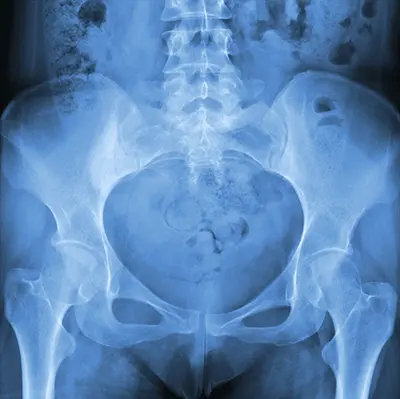

Diagnosis of Athletic Pubalgia

Diagnosing athletic pubalgia can be challenging because groin pain may have multiple causes. Dr. Domb and his team use a combination of medical history, physical examination, and imaging studies to confirm the diagnosis:

- MRI: Provides detailed images of soft tissues, muscles, tendons, and ligaments; considered the most definitive test for athletic pubalgia

- CT Scan: Gives cross-sectional images of the pelvis and groin

- X-rays: Helps rule out fractures

- Ultrasound: Assesses surrounding soft tissues and excludes inguinal hernia

- Bone Scan: Detects bone injury